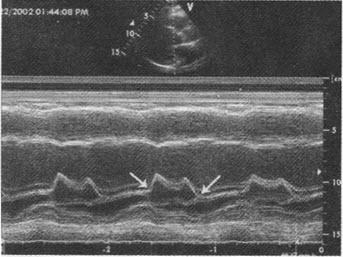

2·m型超声心动图 (1)梗阻者二尖瓣c‐d段呈多层弓背样隆起,称为sam

m型超声心动图显示二尖瓣活动曲线,图中箭头所示两点称为()

sam征阳性M型超声图片

二尖瓣sam征M型示意图

二尖瓣sam征示意图